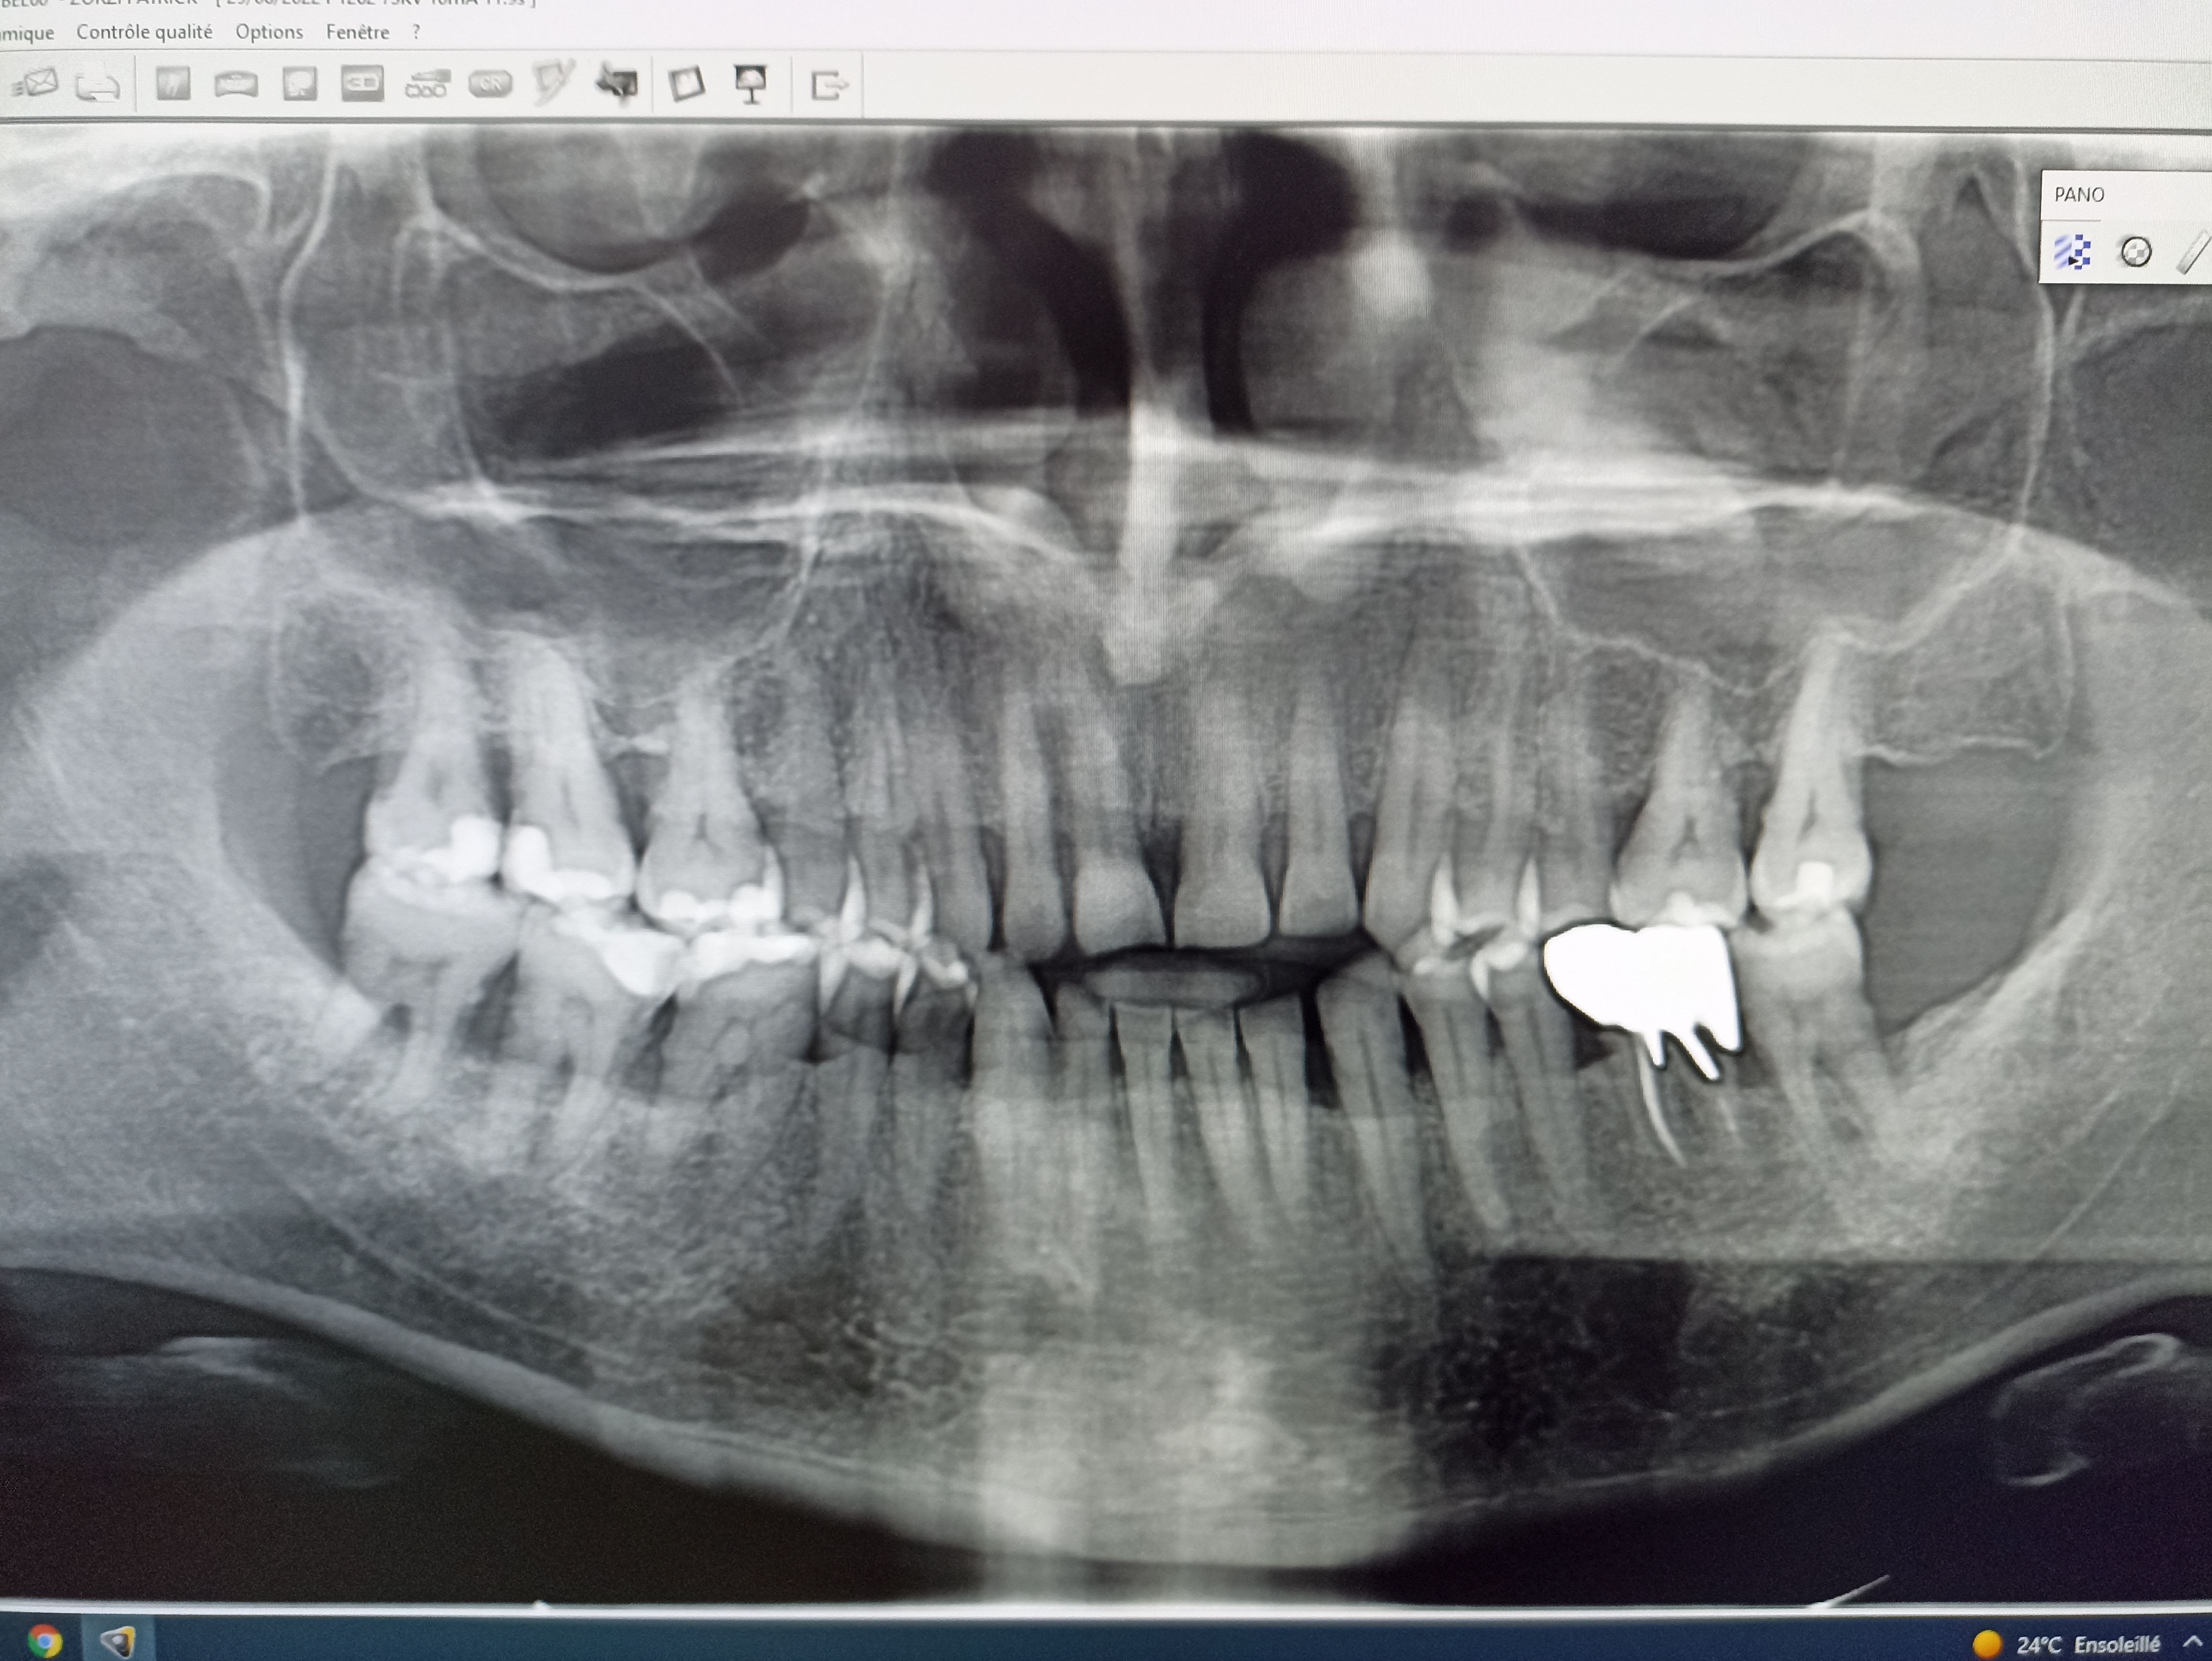

Désolé d'avance pour la qualité des photos.

Juste pour être certain, la 36, elle n'aurait pas été réalisée il y a 2 ans et quelques mois?

et d'accord aussi pour la 36 date de pose ?

Je suis censé le revoir dans quelques semaines, lui avec des photos moi avec des idées. Il va essayer de contacter son ancien dentiste pour obtenir une pano car il ne connait pas l'ancienneté de sa 36 qui est effectivement peu avenante.

Si je parle de la 36, c'est que j'ai déjà vu un cas strictement similaire.

Moyennant quoi, 2 ans plus tard, le patient revient en béance totale, occlusion exclusive sur les 7 et les 8. Les platres s'engrènent presque parfaitement, mais impossible pour le patient de retrouver un contact incisif. Interposition linguale qui aurait stimulé une croissance mandibulaire résiduelle?

Aucune idée, mais le surcontact, lui je l'ai trouvé sur les empreintes, il était sur la 27, qui avait été distalée lors de l'insertion de la 26. C'est con...

Faut dire que là c'est très particulier, on dirait qu'il y a eu ingression des incisives. Je parie quand même très fort sur une parafonction quelconque, mais laquelle?

Pour l'occlusion, j'ai bien essayé de lui trouver des "crouic", des "clang " ou des trucs pas nets par derrière; mais il occluse fort bien, droit et sans hésiter, plutôt sereinement et c'est franchement stable. Les faces occlusales des molaires sont bien dessinées, pas du tout abrasées ou parafonctionnées, mais sans bloquer la diduction. Effectivement la 36 est douteuse mais elle ne m'a pas interpellé en bouche, je lui ai fait la radio après.

Pour le coup il a un bon parodonte bien rose bien ferme et tonique et aucune mobilité. L'atteinte Paro à la radio m'a même surpris. Une bonne hygiène orale également. Probable qu'il aie eu un petit curettage dans sa jeunesse, je n'ai pas eu le temps de lui demander